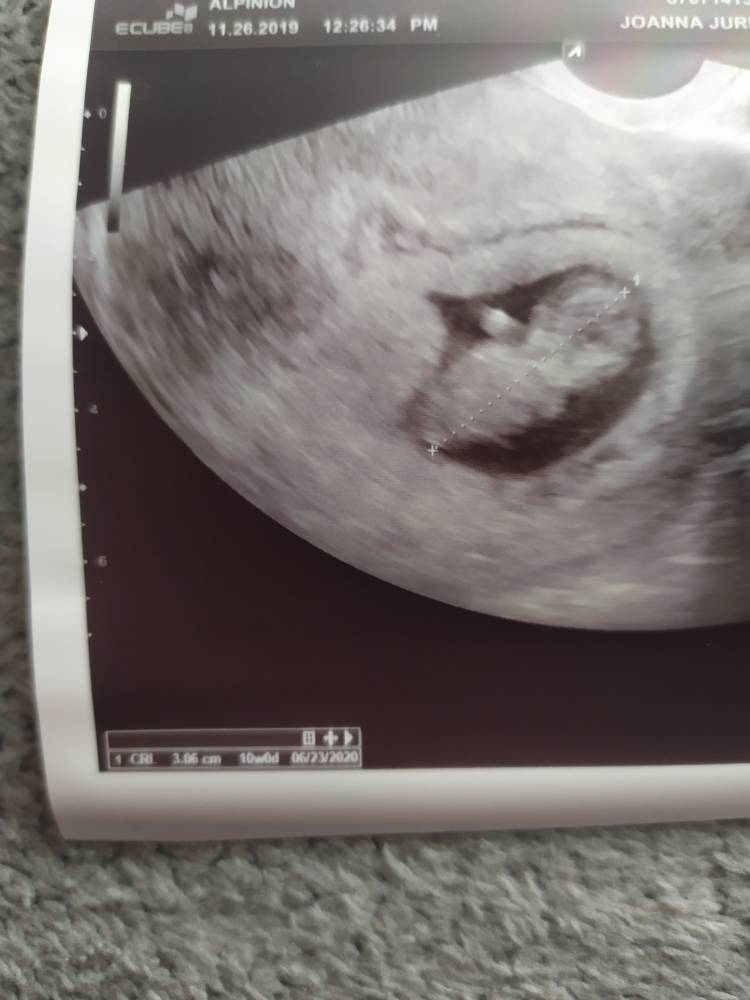

U mnie po wizycie wszystko ok równo 10+0 i 3cm [emoji178]odetchnelam z ulgą.

IMG_20191126_115200.jpeg